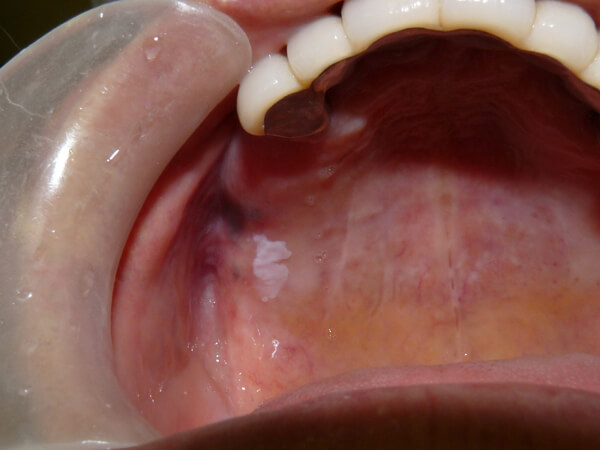

白板症

口腔粘膜疾患にみられる、白い角化性の病変です。比較的頻度も高くみられ、まれに癌化することがあるため、前癌病変といわれています。